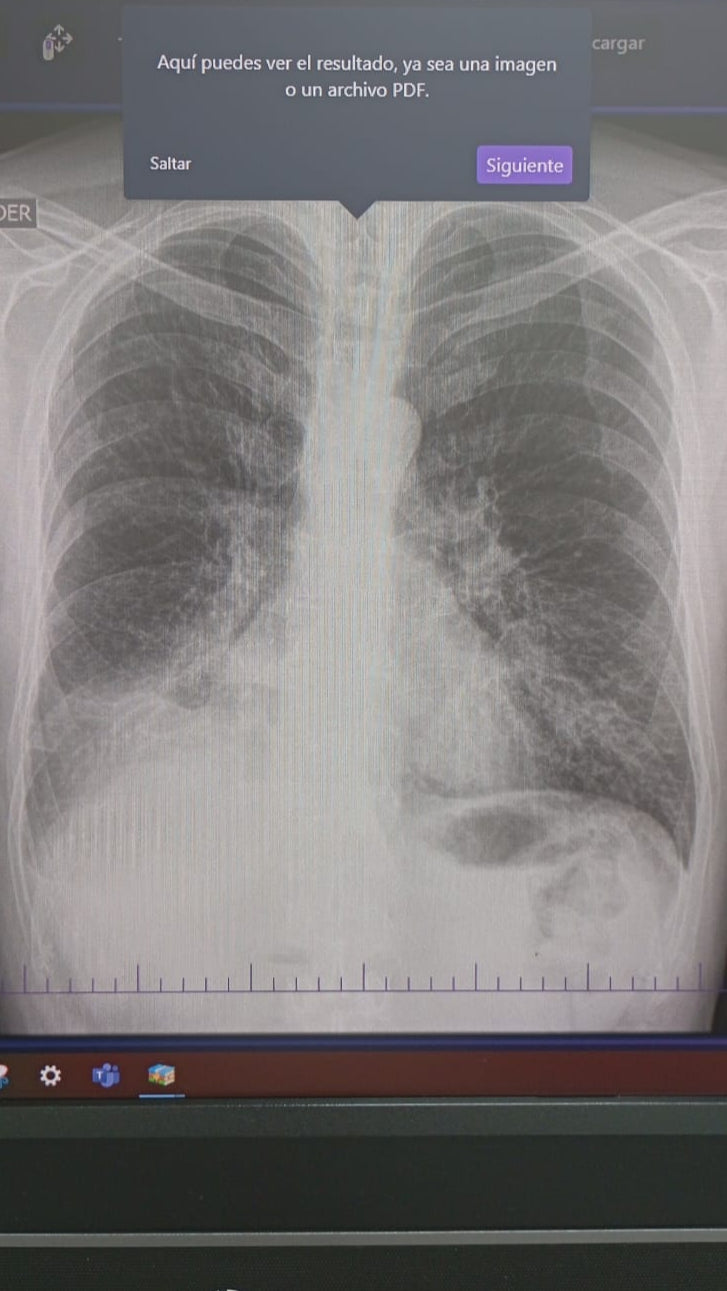

Brain Scan - Scan showing the brain tumor. The small line going through it shows the tumor is growing into two.

Lung Scan (Front View) - Showing the lung tumor activity

In December of 2024, what started as a small cough became our worst nightmare. With limited access to health care, we paid what exams we could out of pocket.Scans confirmed a tumor, this time on his bronchus, where air flows. This tumor was slowly suffocating my dad.He would have coughing episodes so bad he could barely breathe.

My dad had to leave the country in May and 3 months later he has yet to start any treatment.Due to Colombia's healthcare system, that means months of waiting for each test with insurance.While he waited, the cancer spread to his kidney. Now to his brain. Two tumors are causing him to loose feeling from the left side of his face, his mouth, and his eye. He is at risk for paralysis.

He has been hospitalized multiple times, coughing blood, in excruciating pain, all while being thousands of miles away from us. Right now my dad urgently needs radiation, chemotherapy, medications, and housing close to the hospital so he can get treatment safely.